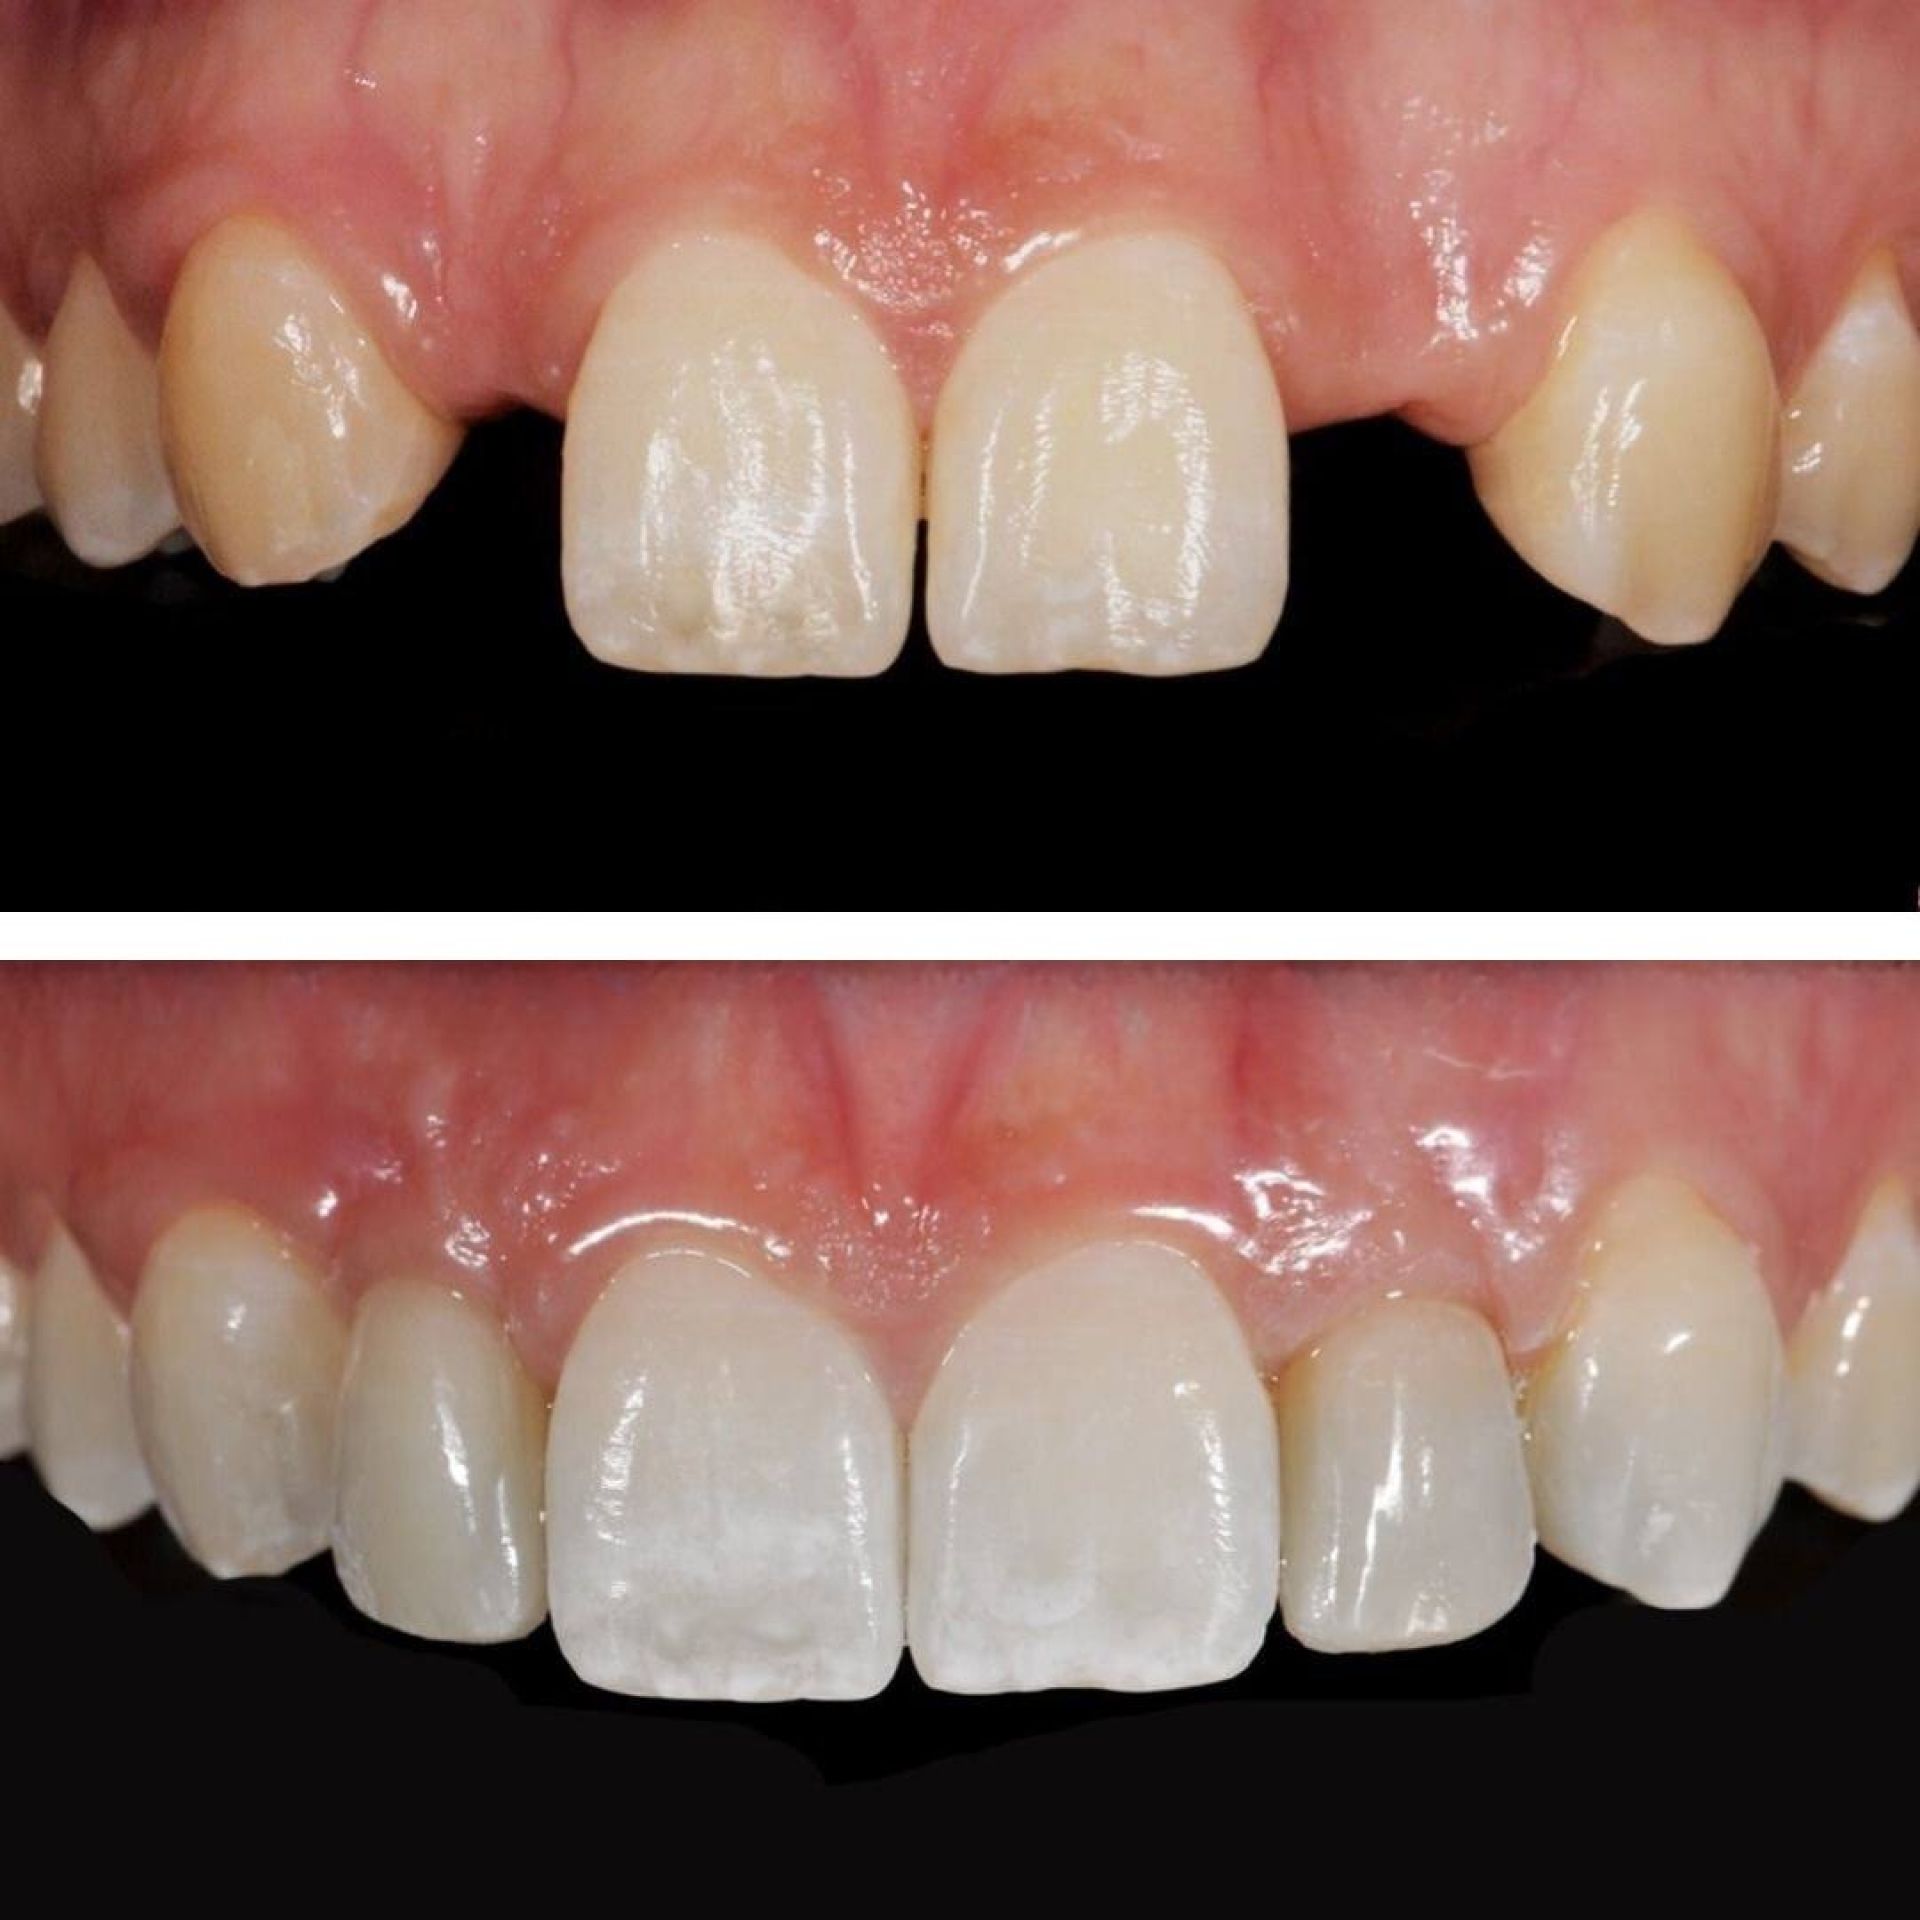

Імплантація зубів — це сучасна технологія відновлення зубного ряду, яка використовується для заміщення втрачених зубів. Цей процес полягає в установці штучного корінця зуба, відомого як імплантат, у кістку щелепи, на який потім кріпиться внутрішньоротова частина — коронка.

Завдяки імплантатам Ви назавжди забудете про дискомфорт, який спричиняє відсутній зуб або зуби. Ми якісно відновимо жування та естетику Вашої посмішки в найкоротші терміни з довготривалим результатом.

- Натуральний вигляд і відчуття

- Довготривале використання

Ці переваги роблять імплантати привабливим вибором для багатьох пацієнтів які шукають найефективніший і тривалий спосіб заміни втрачених зубів.

При належному догляді пацієнти можуть користуватися імплантами протягом багатьох років або навіть десятиліть.